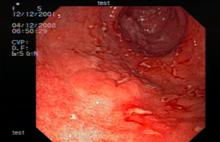

По данным ЭУЗИ, эндосонограммы пациентов со всеми формами лимфом демонстрируют их отличительный признак - в области визуально измененной слизистой оболочки при сканировании стенка желудка утолщена за счет гиперэхогенного неоднородного подслизистого и глубоких слоев слизистого слоя, а между патологическими зонами визуализируются участки нормальной пятислойной стенки желудка (рис.4).

Рис. 4. 58 лет. Язвенно-инфильтративная лимфома. Заключение иммуногистохимии: диффузная В-крупноклеточная лимфома желудка:

а - визуальная картина, требующая дифференциальной диагностики между язвенно-инфильтративным раком и язвенно-инфильтративной лимфомой тела желудка; б - эндосонограмма язвенно-инфильтративной лимфомы желудка, утолщенный гиперэхогенный подслизистый слой достигает 2,9 мм.

В результате сканирования у больных этой группы в 82,8% были найдены признаки лимфом, в 10,3% - признаки рака и в 6,9% мы не могли с полной уверенностью интерпретировать вид опухоли. Обнаруженные эхографические критерии в пользу лимфомы желудка являлись показанием для проведения петлевой или ступенчатой биопсии и выполнения иммуногистохимического исследования.